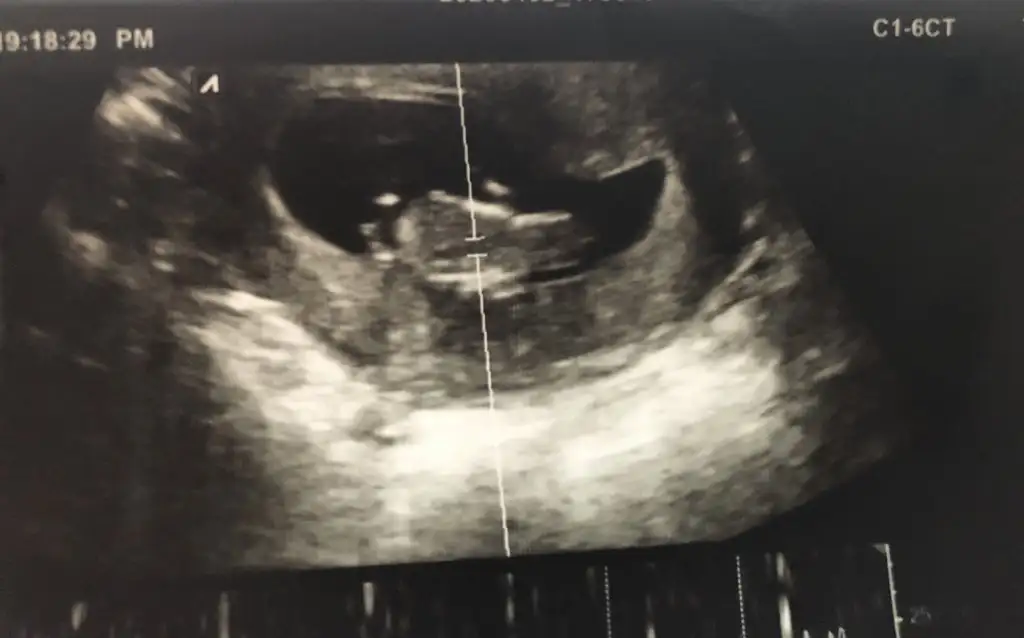

Bugün kontrole gittim doktor bacaklarını açmıyor cinsiyet göremedim dedim ikra meyra sen erkek demistin hep ama bitek bu foto var 14 haftalik bu arada yine varmi tahmin